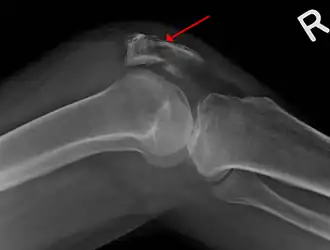

Una fractura de la rótula vista en una vista lateral. | ||

La fractura de rótula, también llamada fractura patelar, es la rotura o pérdida de continuidad ósea del hueso rotuliano. Al encontrarse este hueso en la parte anterior de la rodilla es más propenso al golpe. La mayoría de estas fracturas ocurren como resultado de traumatismos por accidente de tránsito o caída.